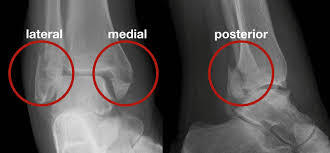

COTTON

= Trimalleolar fracture

- Fracture of the lateral malleolus, fracture of the posterior malleolus, and either a fracture of the medial malleolus or disruption of the deltoid ligament, with visible widening of the mortise on ankle radiograph